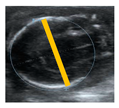

| Biparietal diameter (BPD) | From a transversal visualization of the cranium: Distance from the external side of the parietal bone to the internal side of the opposite parietal bone | mm | ![]() |